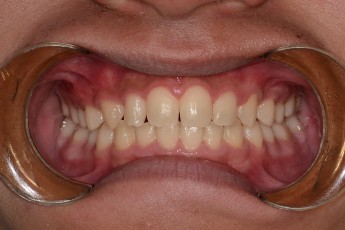

BEFORE & AFTER